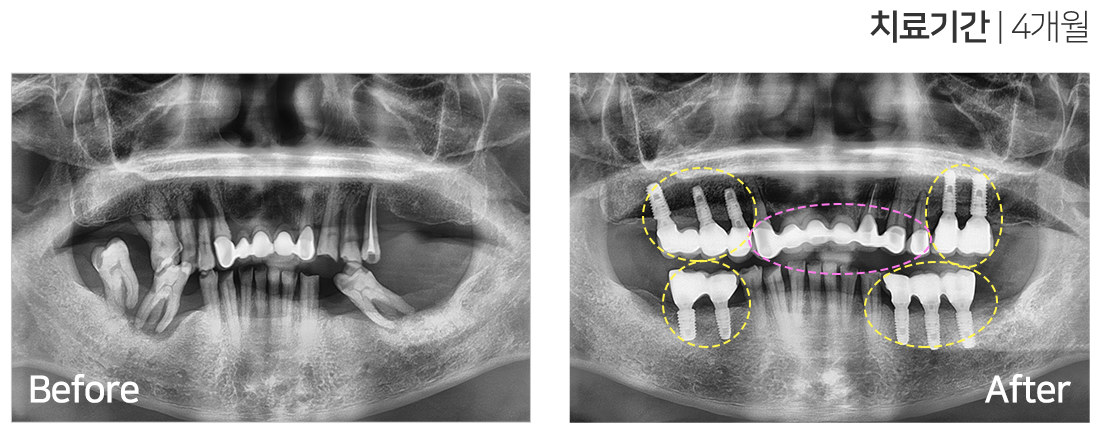

임플란트 시술 사례

IMPLANT TREATMENT CASES

※ 전신질환 및 관리 능력에 따라 임플란트 주위염 등의 부작용이 있을 수 있습니다.